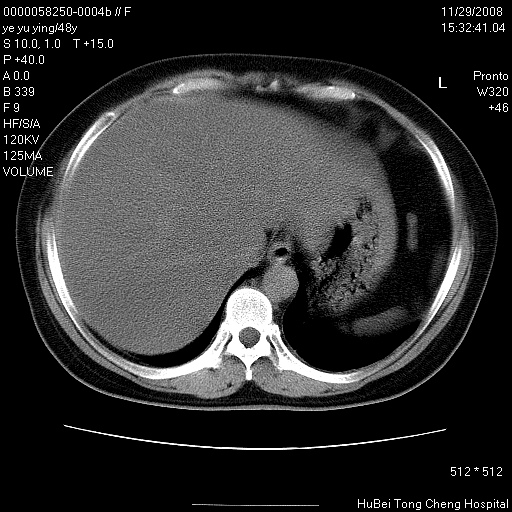

以下是引用zsl6918在2008-11-29 21:47:00的发言:[br]恶性肿瘤病史,转移瘤首先考虑。脂肪肝,胆囊结石。

以下是引用huenhao在2008-11-29 22:11:00的发言:[br]脂肪肝,胆囊结石。左肺病灶建议定期复查。

以下是引用liuyue在2008-11-30 5:44:00的发言:[br]1.左肺病变,首先考虑感染性病变,转移待排;建议治疗后复查。[br]2.肝脏密度普遍减低,考虑与化疗有关。[br]3.胆囊结石.